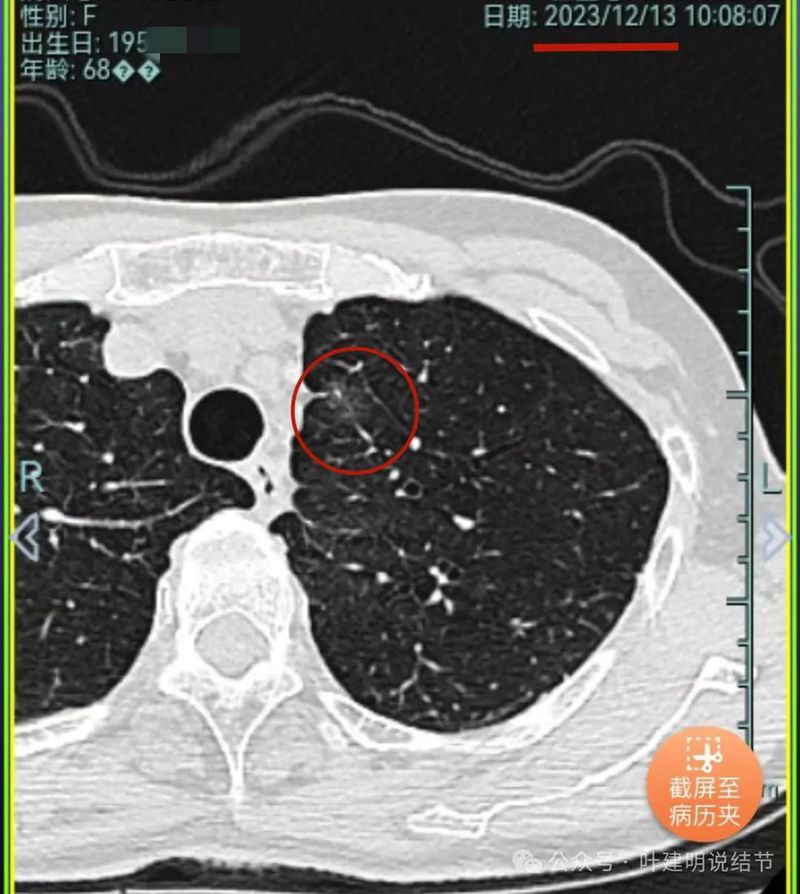

先来看2019年时的影像:

病灶1:右上叶磨玻璃密度结节,略偏长条状,有微小血管进入,轮廓与边界较清。

病灶2:右下叶磨玻璃结节,边缘不平毛糙,没有实性成分,轮廓与边界较清楚。

病灶3:右中叶混合密度结节,有分叶征,有收缩力,整体轮廓与边界清。

病灶4:右中叶伴钙化结节,考虑良性。

病灶5:右中叶磨玻璃病灶,轮廓与边界稍显模糊,灶内有支气管扩张的样子,贴叶间裂较近。

病灶6:左上叶淡磨玻璃结节,轮廓较清,密度较低。

病灶7:左下叶胸膜下结节,大部分磨玻璃密度,只是不太均匀,说不上明显的实性成分,整体轮廓与边界较清。此灶当年已经切除,从术后影像来看,大概是段切除可能性大些。

2023年12月又有复查,我们只看左上这处:

密度仍低,灶内有血管穿行,但说不上较前明显的进展,总体密度来看,风险仍不大。但这时候,患者选择做了此灶的消融。